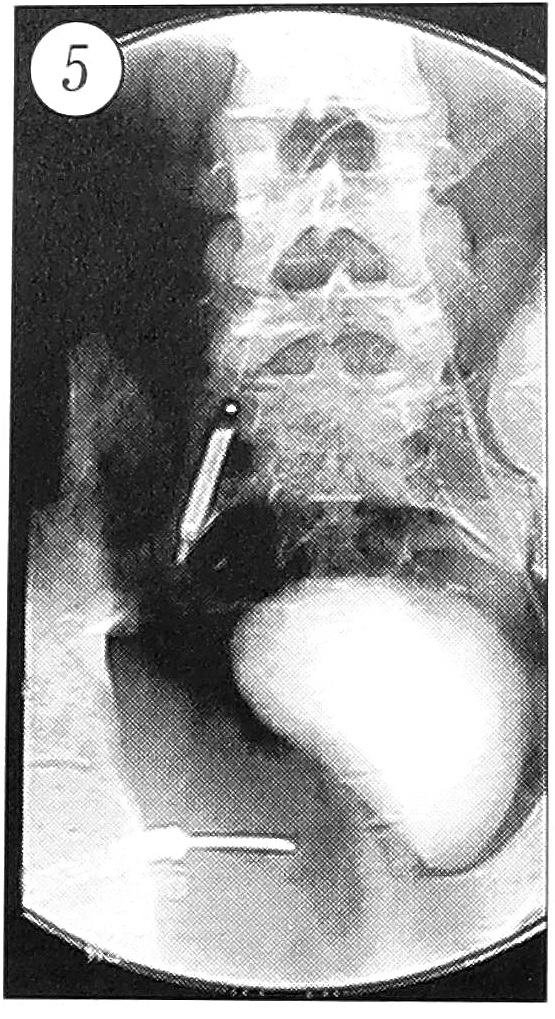

Произведена временная окклюзия внутренней подвздошной артерии баллонным катетером 6,0 × 30 мм (рис. 5). Повторно измерено внутрикистное давление — 500 мм вод. ст. (рис. 4, б). Для выявления возможного вовлечения в патологический процесс мочевого пузыря предпринято контрастирование очага омнипаком (20 мл): стенки пузыря оказались интактными (рис. 6).

Рис. 5. Окклюзия внутренней подвздошной артерии баллонным катетером.